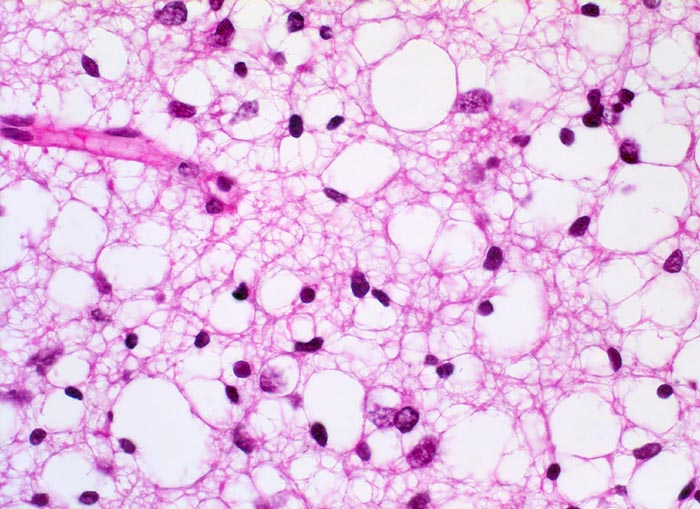

PathoPic ID 5259 - Oligodendrogliom (WHO Grad II)

Oligodendrogliom (WHO Grad II)

Tumorzellen mit runden Kernen und klarem Zytoplasma.

Kapilläres Gefäss

Kopfschmerzen und epileptische Anfälle seit zwei Jahren.

Histologie

400